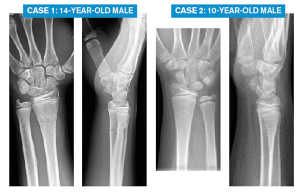

Case 1: 14-year-old male Case 2: 10-year-old male

Case 1: 14-year-old male

Case 2: 10-year-old male